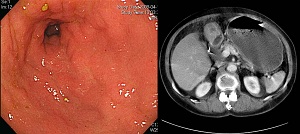

[Antral type Borrmann type IV (4) - More cases with peritoneal seeding]

ÀüÁ¤ºÎ¿¡ ±¹ÇÑµÈ º¸¸¸ 4Çü ÁøÇàÀ§¾ÏÀº óÀ½ºÎÅÍ peritoneal seedingÀ» µ¿¹ÝÇÑ °æ¿ì°¡ ÀûÁö ¾Ê½À´Ï´Ù. ÀÌÀ¯´Â ¸ð¸£°Ú½À´Ï´Ù.

peritoneal seeding (+)